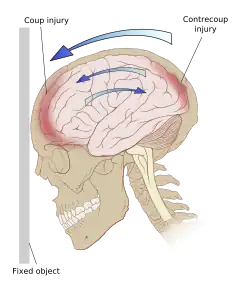

El TCE es causado por fuerzas externas a la cabeza que pueden clasificarse como fuerzas de contacto y de inercia. Las fuerzas de contacto suelen causar lesiones focales como fracturas de cráneo, contusiones y hematomas como el epidurales o subdurales. Cuando la inercia actúa sobre la cabeza causa aceleración por traslación o rotación con o sin una fuerza de contacto. Este es el caso de los «latigazos» que se producen cuando se frena bruscamente un vehículo. Dado que el cerebro no está rígidamente unido al cráneo, el movimiento de traslación por inercia del cerebro en la cavidad craneal puede causar contusiones, hematomas intracerebrales y hematomas subdurales, por impacto de la masa encefálica con las estructuras craneales. La inercia por rotación o angular suele tener un efecto más importante y puede causar daño axonal difuso. Un TCE grave puede ser resultado solamente de fuerzas de aceleración/desaceleración sin daño alguno en el cuero cabelludo.[3][15]

Existen dos tipos de daño primario: el traumatismo craneal cerrado (TCC) y el traumatismo craneal penetrante (TCP). En el TCC el impacto directo del cerebro contra el cráneo y el corte de las estructuras neurovasculares por las fuerzas de rotación o de rebote dan como resultado el daño en el cuerpo celular y los axones. Los accidentes de tráfico son colisiones a alta velocidad muy rápida y son particularmente perjudiciales debido a que las estructuras neuronales, que residen en un compartimento lleno de líquido, se mueven durante la parada repentina del cuerpo en movimiento chocando contra la bóveda craneal. Las estructuras se golpean tanto en el plano directo como en el opuesto del movimiento contra la lámina ósea interna. Esta es la base del patrón de lesión por golpe-contragolpe donde se ve una lesión contusional o en el cerebro profundo que el lugar del impacto del cráneo y 180 grados opuesto al lugar del impacto. Si hay fuerzas de rotación, las estructuras se tuercen y pueden ocurrir desgarre. Esta es la causa de la lesión axonal difusa y se ve comúnmente en TAC o MRI como hemorragias después del TCE[8]

Las contusiones se encuentran en 20% al 25% de los pacientes con TCE grave. Son lesiones heterogéneas compuestas de zonas de hemorragia puntiforme, edema y necrosis que aparecen en las imágenes de TC como áreas de hiperdensidad puntiforme (hemorragias), con hipodensidad circundante (edema), suelen estar localizadas en la cara inferior del lóbulo frontal y la cara anterior del lóbulo temporal por su relación con el ala mayor del esfenoides. También se pueden encontrar en la superficie de impacto y en la superficie contraria a este, el llamado efecto golpe-contragolpe. Cuando estas evolucionan se parecen más a los hematomas intracerebrales y su ubicación depende el posible efecto de masa.